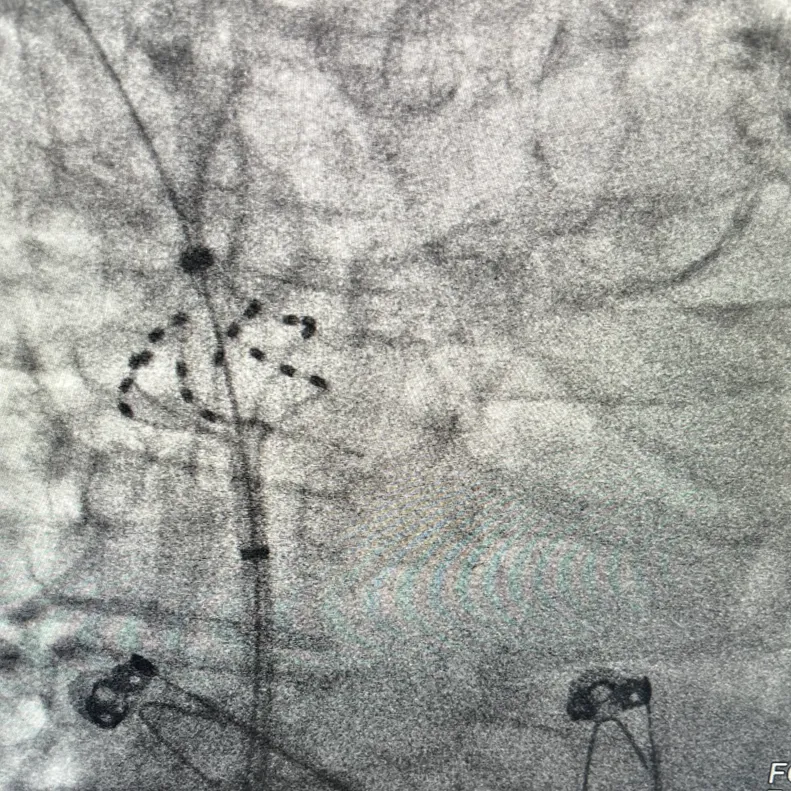

六瓣花导管呈网篮及花瓣形态放电

LSPV消融及前后电位对比

LIPV消融及前后电位对比

RSPV消融及前后电位对比

RIPV消融及前后电位对比

后壁消融及前后电位对比

上腔静脉消融及前后电位对比